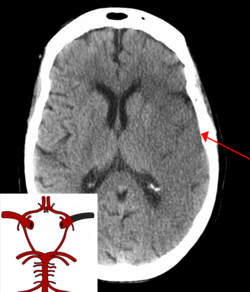

CT scan of the brain showing a prior right-sided ischemic stroke from blockage of an artery. Changes on a CT may not be visible early on.[1]

The biggest risk factor for stroke is high blood pressure.[7] Other risk factors include high blood cholesterol, tobacco smoking, obesity, diabetes mellitus, a previous TIA, end-stage kidney disease, and atrial fibrillation.[2][7][8] Ischemic stroke is typically caused by blockage of a blood vessel, though there are also less common causes.[13][14][15] Hemorrhagic stroke is caused by either bleeding directly into the brain or into the space between the brain's membranes.[13][16] Bleeding may occur due to a ruptured brain aneurysm.[13] Diagnosis is typically based on a physical exam and supported by medical imaging such as a CT scan or MRI scan.[9] A CT scan can rule out bleeding, but may not necessarily rule out ischemia, which early on typically does not show up on a CT scan.[10] Other tests such as an electrocardiogram (ECG) and blood tests are done to determine risk factors and rule out other possible causes.[9] Low blood sugar may cause similar symptoms.[9]

CT scan of an intraparenchymal bleed (bottom arrow) with surrounding edema (top arrow)